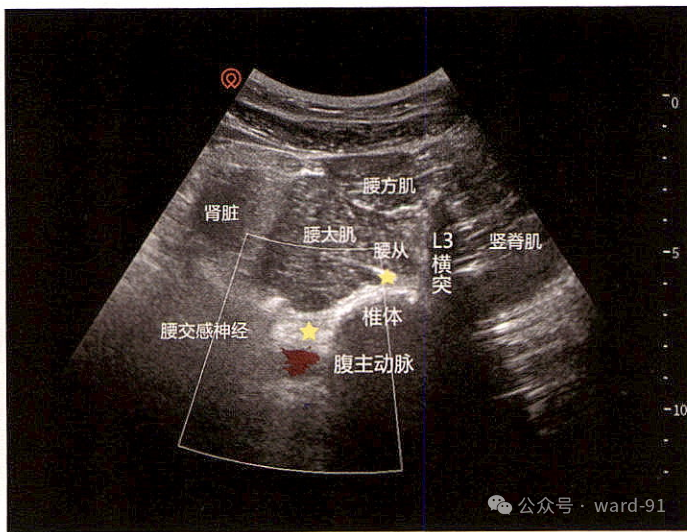

切面:将低频探头横切置于腋中线,L3横突切面

| 骨 | L3横突;L3横突腹侧深面的强回声骨皮质影像为L3椎体中部 |

| 肌肉 | 腰大肌、竖脊肌及腰方肌的“三叶草”结构超声图像 |

| 神经 | 腰交感神经位于腰大肌深面,椎体与腹主动脉之间的区域 |

| 血管 | 椎体前方的腹主动脉; |